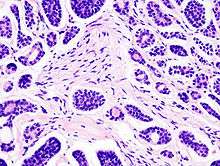

Micrograph of an adenoid cystic carcinoma of a salivary gland (right of image). Normal serous glands, typical of the parotid gland, are also seen (left of image). H&E stain. | |

![]() Histopathological image of adenoid cystic carcinoma of the salivary gland. Hematoxylin & eosin stain. |